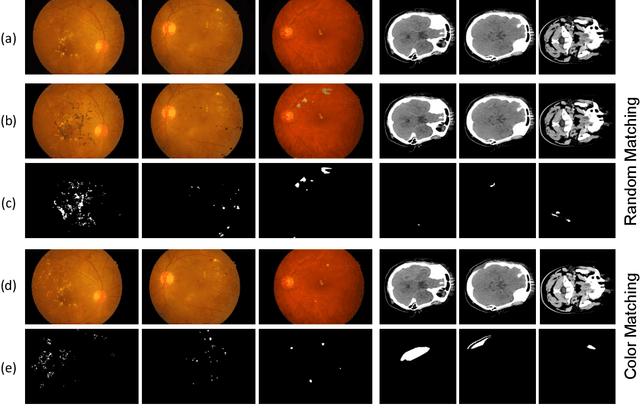

Abstract:Semi-supervised learning has the potential to improve the data-efficiency of training data-hungry deep neural networks, which is especially important for medical image analysis tasks where labeled data is scarce. In this work, we present a simple semi-supervised learning method for lesion segmentation tasks based on the ideas of cut-paste augmentation and consistency regularization. By exploiting the mask information available in the labeled data, we synthesize partially labeled samples from the unlabeled images so that the usual supervised learning objective (e.g., binary cross entropy) can be applied. Additionally, we introduce a background consistency term to regularize the training on the unlabeled background regions of the synthetic images. We empirically verify the effectiveness of the proposed method on two public lesion segmentation datasets, including an eye fundus photograph dataset and a brain CT scan dataset. The experiment results indicate that our method achieves consistent and superior performance over other self-training and consistency-based methods without introducing sophisticated network components.